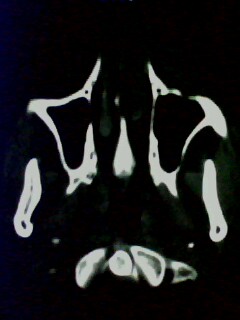

以下是引用随光逐影在2009-5-20 19:22:00的发言:[br]1)考虑左上颌骨近中线区含牙囊肿。2)鼻中隔右突偏曲。3)双侧下鼻甲肥大。

以下是引用余辉在2009-5-20 19:35:00的发言:[br]1)考虑左上颌骨近中线区含牙囊肿。2)鼻中隔右突偏曲。3)双侧下鼻甲肥大。[br]支持,不除外上颌骨正中囊肿,有窦道通鼻前庭,出血可能是内部有感染,图像不是很清,可照个片看一下